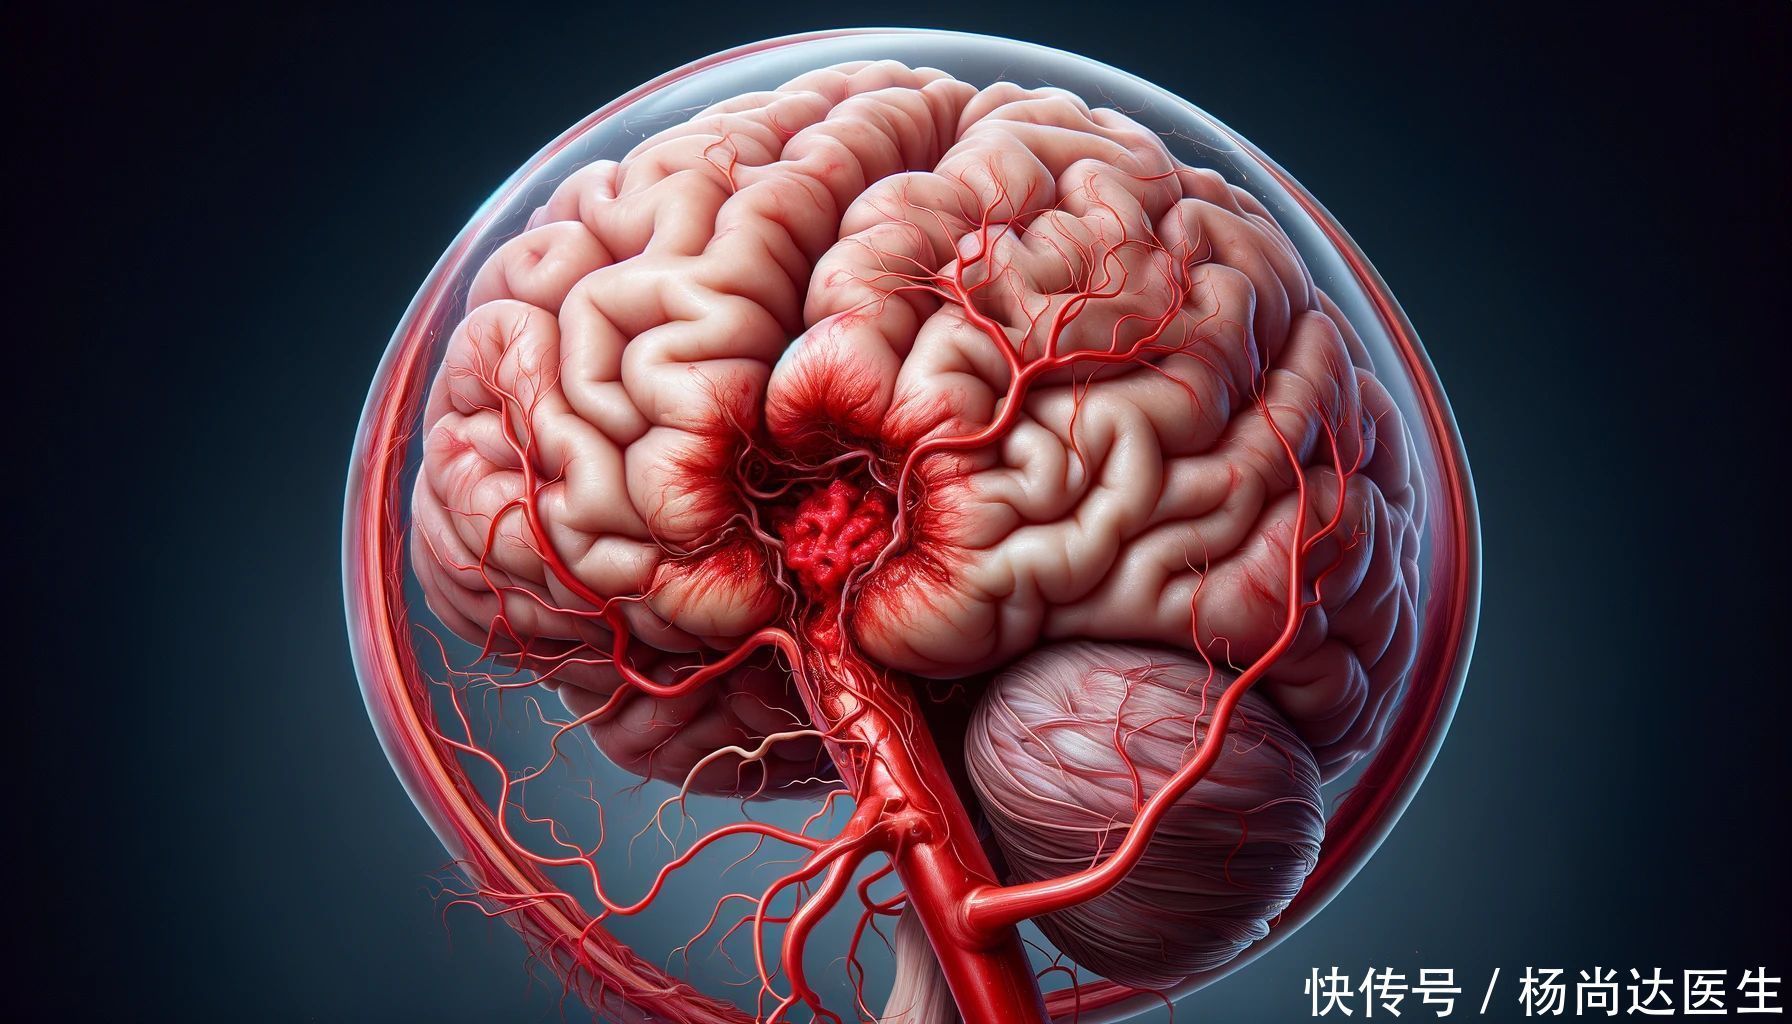

王先生的同事们可能很难想象,这个平日里看似健康的人,竟然会突然倒下。但医生告诉他们,王先生遭遇的,是脑出血这一神经系统危重病。脑出血,如同潜伏在脑海深处的幽灵炸弹,悄无声息地引爆,其破坏力惊人,对患者的生命安全与健康状态构成了严峻的挑战。

脑出血,简而言之,即脑血管意外崩裂,血流如注,侵袭至脑实质或蛛网膜下腔,造成脑部组织受损,功能严重受损,危及生命。急性脑卒中,作为一个宽泛的概念,涵盖了两种主要状况:一是脑血管的突然破裂引发的脑出血,二是脑部血液供应不足所致的脑缺血。脑出血与脑缺血均会切断大脑的氧气供应,导致脑部功能受损,并随后触发一连串严重的并发症。